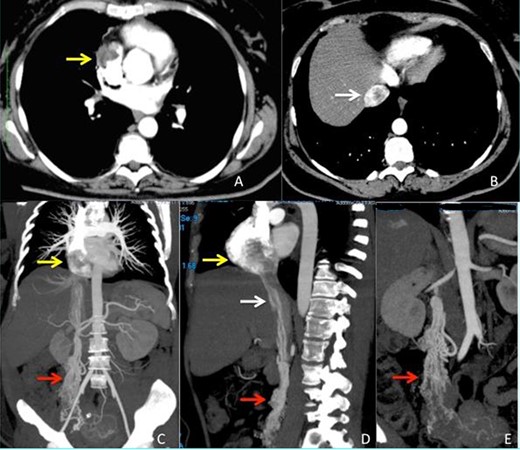

A 52-year-old woman was transferred to our department with a diagnosis of right atrial thrombus and mild right cardiac insufficiency. Her complaint was due to a mass in her IVC extending through the right atrium and abutting in the right ventriculum, highly suspect for a thrombus. CT scan revealed a mass arising from the right adnexa that via the right densely enhancing vascular structures of the ovarian veins reached the IVC and right atrium forming the intracardiac mass (Fig. 1). The preoperative work-up consisted of transoesophageal ultrasonography that showed a free-floating echogenic right intraatrial mass measuring 70 × 50 mm originating from the IVC and protruding in the right ventriculum through the tricuspid valve. Cardiac MRI confirmed the presence and features of the mass (Fig. 2).

CT scan images (A–B) arterious phase showing the defect inside right atrium (yellow arrow) and intrahepatic inferior vena cava (white arrow) due to the presence of the intravascular leimyoma. (C–D) vascular CT reconstruction of the ovarian veins (red arrow), inferior vena cava (white arrow) and right atrium (yellow arrow) stored with the intravascular leiomyoma. (E) Particular view of the ovarian veins (red arrow) with the origin from the right uterine aspect.